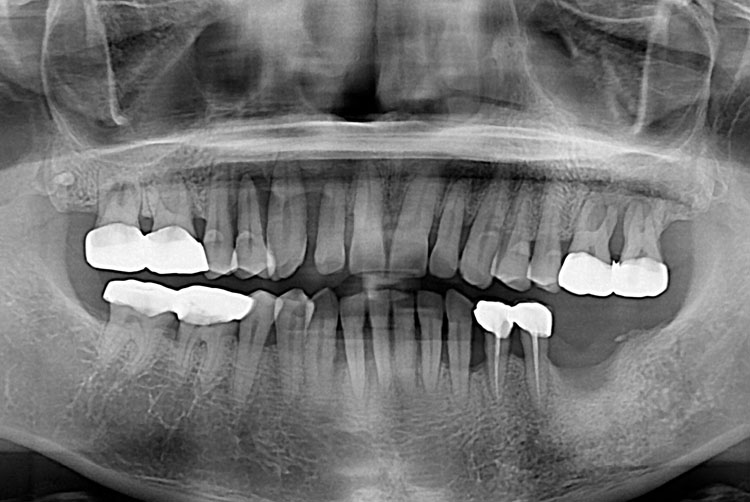

치료전 : 2018-08-16